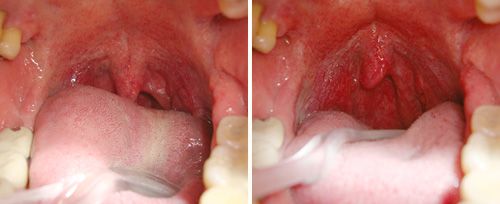

La terapia NightLase® de Fotona es un tratamiento láser no invasivo y amigable para el paciente que aumenta la calidad del sueño del paciente. NightLase® reduce los efectos de la apnea del sueño y disminuye la amplitud de los ronquidos por medio de un suave efecto de tensado inducido por el láser causando la contracción del colágeno en el tejido de la mucosa oral.

La modalidad de láser Er:YAG patentada por Fotona optimiza la  longitud de los pulsos láser, permitiendo la penetración segura de calor en el  tejido de la mucosa oral. Es lo suficientemente suave para ser utilizado en el  tejido sensible dentro de la boca, pero lo suficientemente fuerte como para  proporcionar un calentamiento clínicamente eficaz.

NightLase® es fácil de usar para cualquier médico o dentista, posee una alta tasa de éxito en la producción de cambios positivos en los patrones de sueño. La investigación ha demostrado que NightLase® reduce y atenúa el ronquido y proporciona una forma eficaz, no invasiva para disminuir los efectos de la apnea del sueño.